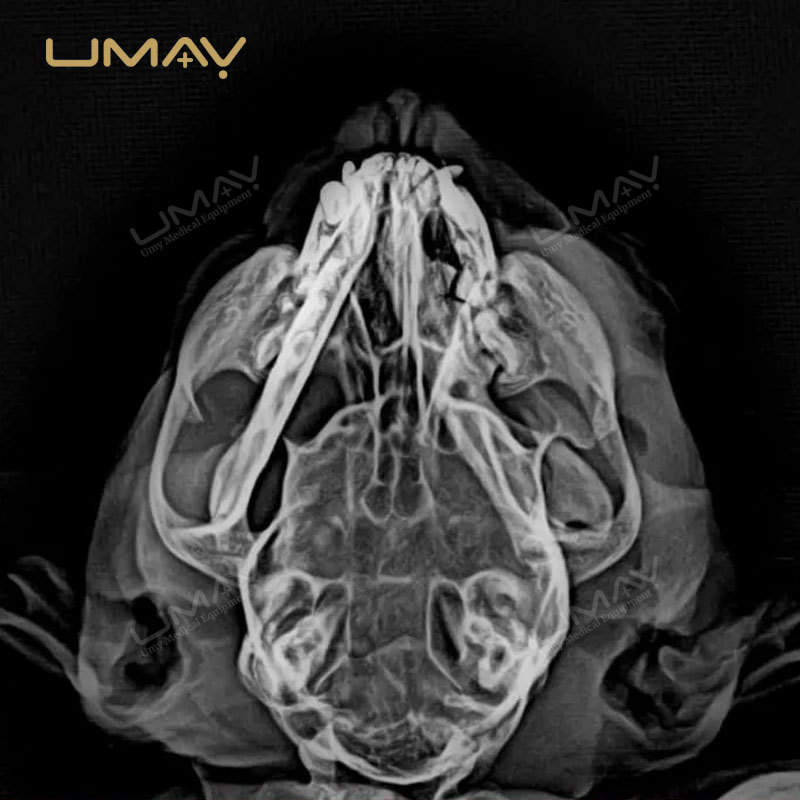

Detector de paneles planos digitales 1417 para radiología de rayos X veterinarios

El detector digital de panel plano 1417 para radiología veterinaria está diseñado para proporcionar imágenes de alta resolución que permiten diagnósticos precisos en una amplia variedad de animales. Su avanzada tecnología DR garantiza una captura rápida y eficiente, reduciendo la exposición a la radiación sin comprometer la calidad de imagen.

Gracias a su diseño ligero y portátil, este detector se integra fácilmente en sistemas de rayos X veterinarios existentes, lo que lo convierte en una opción ideal tanto para clínicas fijas como para servicios móviles. Su versatilidad permite realizar estudios radiológicos en animales pequeños, medianos y grandes, optimizando el flujo de trabajo en entornos de alta demanda.

El panel plano 1417 ofrece una excelente relación señal-ruido y rápida transferencia de imágenes, lo que mejora la eficiencia diagnóstica y reduce los tiempos de espera. Además, su estructura robusta y duradera garantiza un rendimiento confiable incluso en entornos de uso intensivo.

Este detector es una herramienta esencial para clínicas veterinarias modernas que buscan calidad de imagen superior, rapidez operativa y seguridad en los procedimientos, contribuyendo a diagnósticos más precisos y a una mejor atención animal.